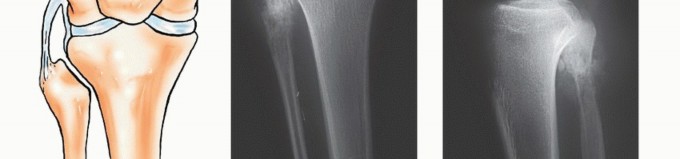

The Type I resection, classified under the Malawer oncologic surgical staging system as a proximal fibulectomy or marginal en bloc resection of the proximal fibula, has emerged as the gold standard for managing these complex lesions. When executed precisely, this procedure allows for complete tumor extirpation while preserving functional limb biomechanics and avoiding the profound psychological and physiological morbidity of amputation.

Epidemiologically, tumors of the fibula account for a relatively small fraction of all primary bone neoplasms. When tumors do manifest in this bone, they exhibit a strong predilection for the proximal fibula, followed by the fibular diaphysis, and least commonly, the distal fibula. A comprehensive review of institutional musculoskeletal oncology registries demonstrates a specific histologic distribution for proximal fibular tumors. Benign aggressive lesions, specifically giant cell tumors of bone (GCTs) and aneurysmal bone cysts (ABCs), are the most frequently encountered pathologies in this anatomic region.

Among malignant primary bone tumors, chondrosarcoma and osteosarcoma constitute the majority of cases, followed closely by Ewing sarcoma in the pediatric and adolescent populations. Benign osteochondromas and enchondromas also frequently present in the proximal fibular metaphysis and must be monitored for malignant transformation. Metastatic carcinomas to the fibula (e.g., lung, breast, prostate, renal, and thyroid) remain exceedingly rare but must be considered in the differential diagnosis of a destructive, permeative fibular lesion in an older adult.

The primary indications for a Type I fibular resection include high-grade primary bone sarcomas (such as osteosarcoma, Ewing sarcoma, and dedifferentiated chondrosarcoma) localized to the proximal fibula without encasement of the major neurovascular structures. Additionally, aggressive benign tumors, such as Campanacci Grade III giant cell tumors or recurrent aneurysmal bone cysts that have destroyed the fibular head cortex and cannot be managed with intralesional curettage, are excellent candidates for this procedure. Isolated solitary metastases to the proximal fibula in patients with controlled systemic disease may also be managed with a palliative or curative-intent en bloc resection.